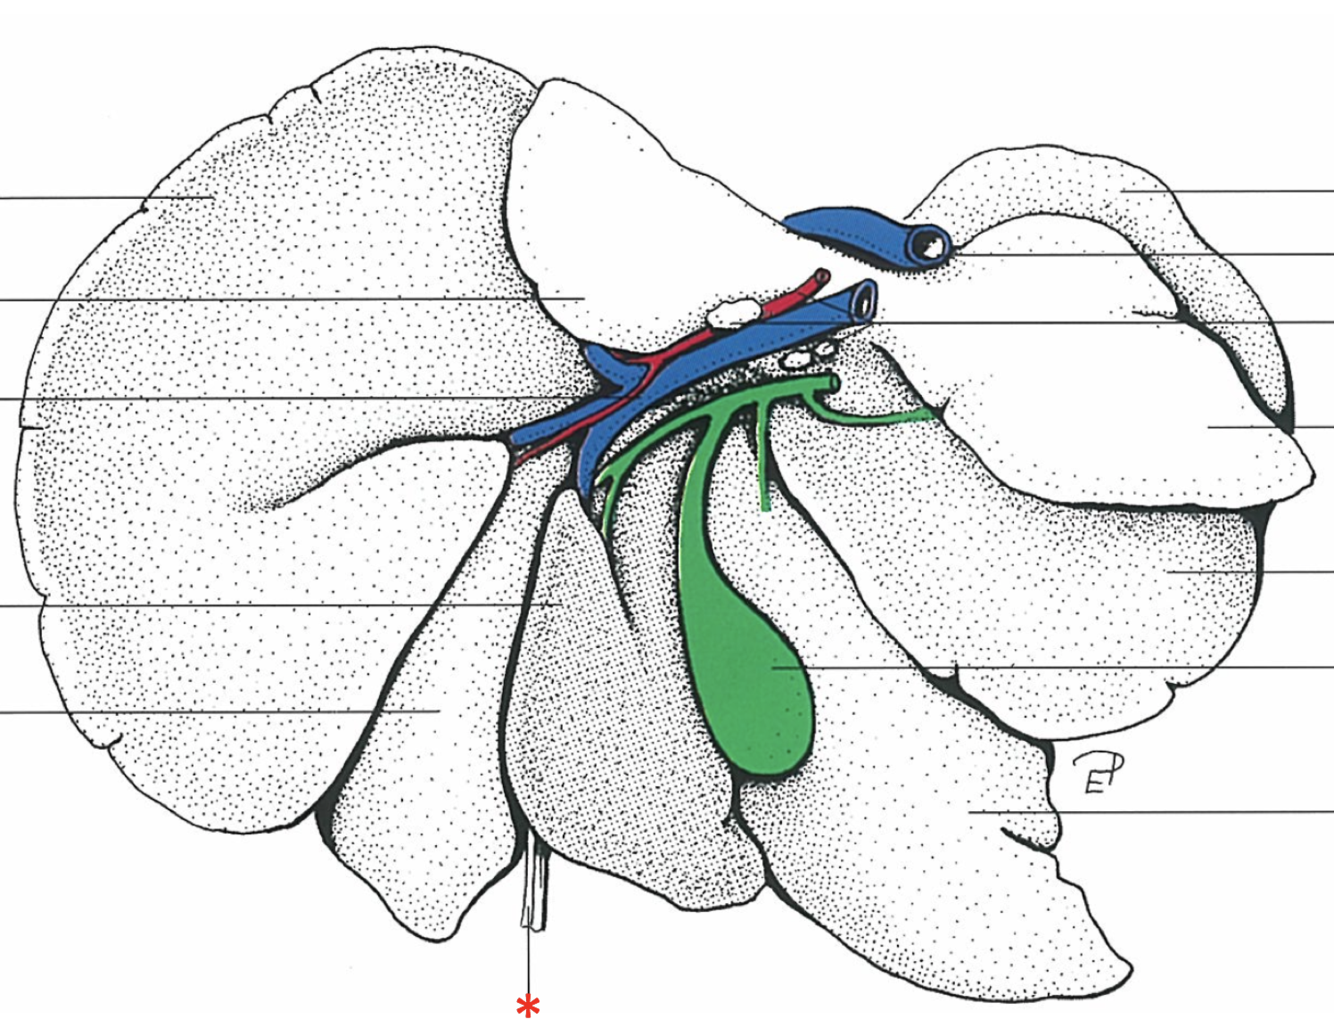

Porta hepatis

- With v. portae et a. hepatica

Lobus caudatus

Lobus quadratus

Lobus hepatis sinister medialis

Lobus hepatis dexter medialis

Lobus hepatis dexter lateralis

Proc. caudatus

V. portae

Proc. papillaris

Lobus hepatis sinister lateralis

Impressio renalis

What is shown? Give the Aspect.

Liver of a Cat

Fascies visceralis

Dorsal Aspect

Area nuda

- Not covered by serous membrane